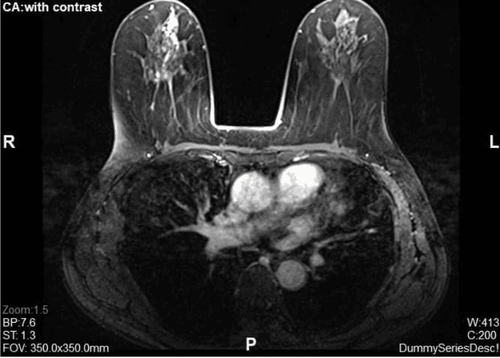

Spectacular journey: Resection of a 5cm giant breast tumor through a 3mm incision